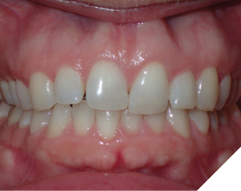

The majority of the orthodontic practices offer a period of “supervised retention” to their patients and communicates the customized retention recommendation with the patient’s general dentists. It is extremely important to work as a team to achieve long term clinical success in maintaining a functional bite and aesthetic smile. The general dentists continue to see their patients on a regular basis and have an opportunity to assess the orthodontic retainers and the bite after the supervised retention period is completed by the orthodontists. With great care, orthodontic retainers would serve for a long time (Fig. 1) without any major issues. However, in some cases, the failure to notice the clinical problems early on results in functional issues that would require a comprehensive orthodontic treatment to correct it (Fig. 2).

Fig. 1A

Fig. 1B

Fig. 1C